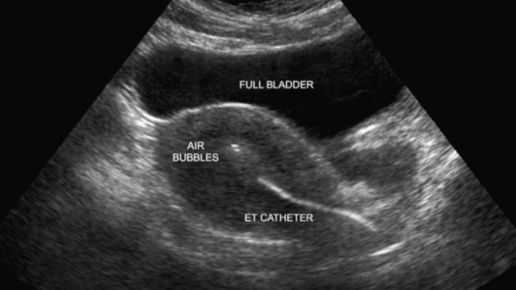

Топ-10 интересных фактов о переносе эмбрионов под контролем УЗИ

Цель успешного переноса эмбрионов - доставить эмбрион(ы) в матку, не повредив их. Исторически перенос эмбрионов осуществлялся с помощью специального катетера, который продвигался до контакта с верхней частью полости матки (дном матки), затем катетер выводился на 5-10 мм перед выбросом эмбрионов. С использованием ультразвука стало очевидно, что при такой «слепой» технике катетер плохо устанавливается в 20% случаев. За последние два десятилетия эта техника была в значительной степени усовершенствована ультразвуковым наведением...